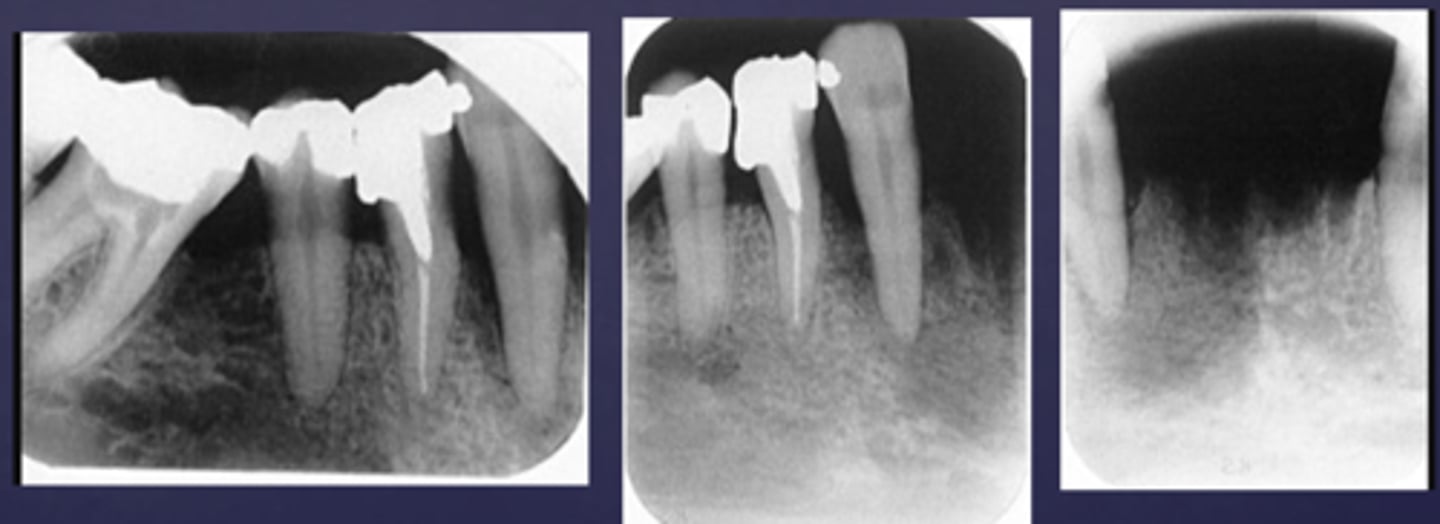

What type of change is seen in this radiograph?

early change (apical periodontitis #30)

early change (apical periodontitis #21)

early change (apical periodontitis #17-18)

early change (apical periodontitis #14)